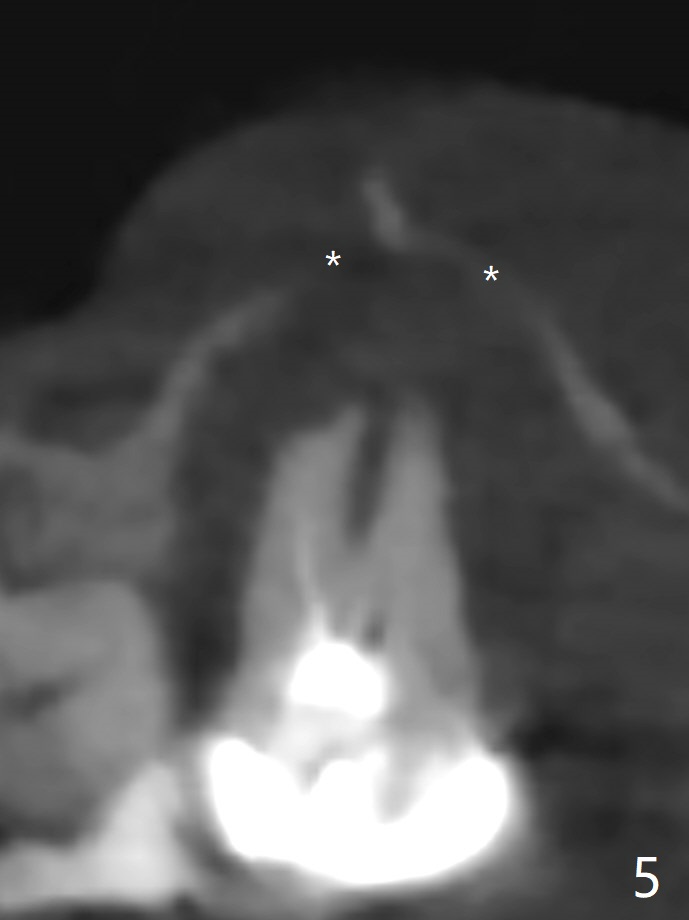

59岁女右上七骨质吸收严重(图一),上颌窦底板薄(图二:*),而窦膜厚(图三:*),应该容易提升,腭侧根吸收(图四:P),上颌窦底板穿孔(图五:*),拔牙后(图六:黑色),水提升(白箭头),放置PRF膜(黄色曲线)和粘性骨块(红色圆圈),最后完成位点保留(图七:大圆圈),放置另外一块PRF膜和6个月吸收膜,缝合,牙周或者树脂敷料。Return to No Deviation 19-21 位点保留后 导板与张口度 Xin Wei, DDS, PhD, MS 1st edition 09/09/2020, last revision 01/01/2021